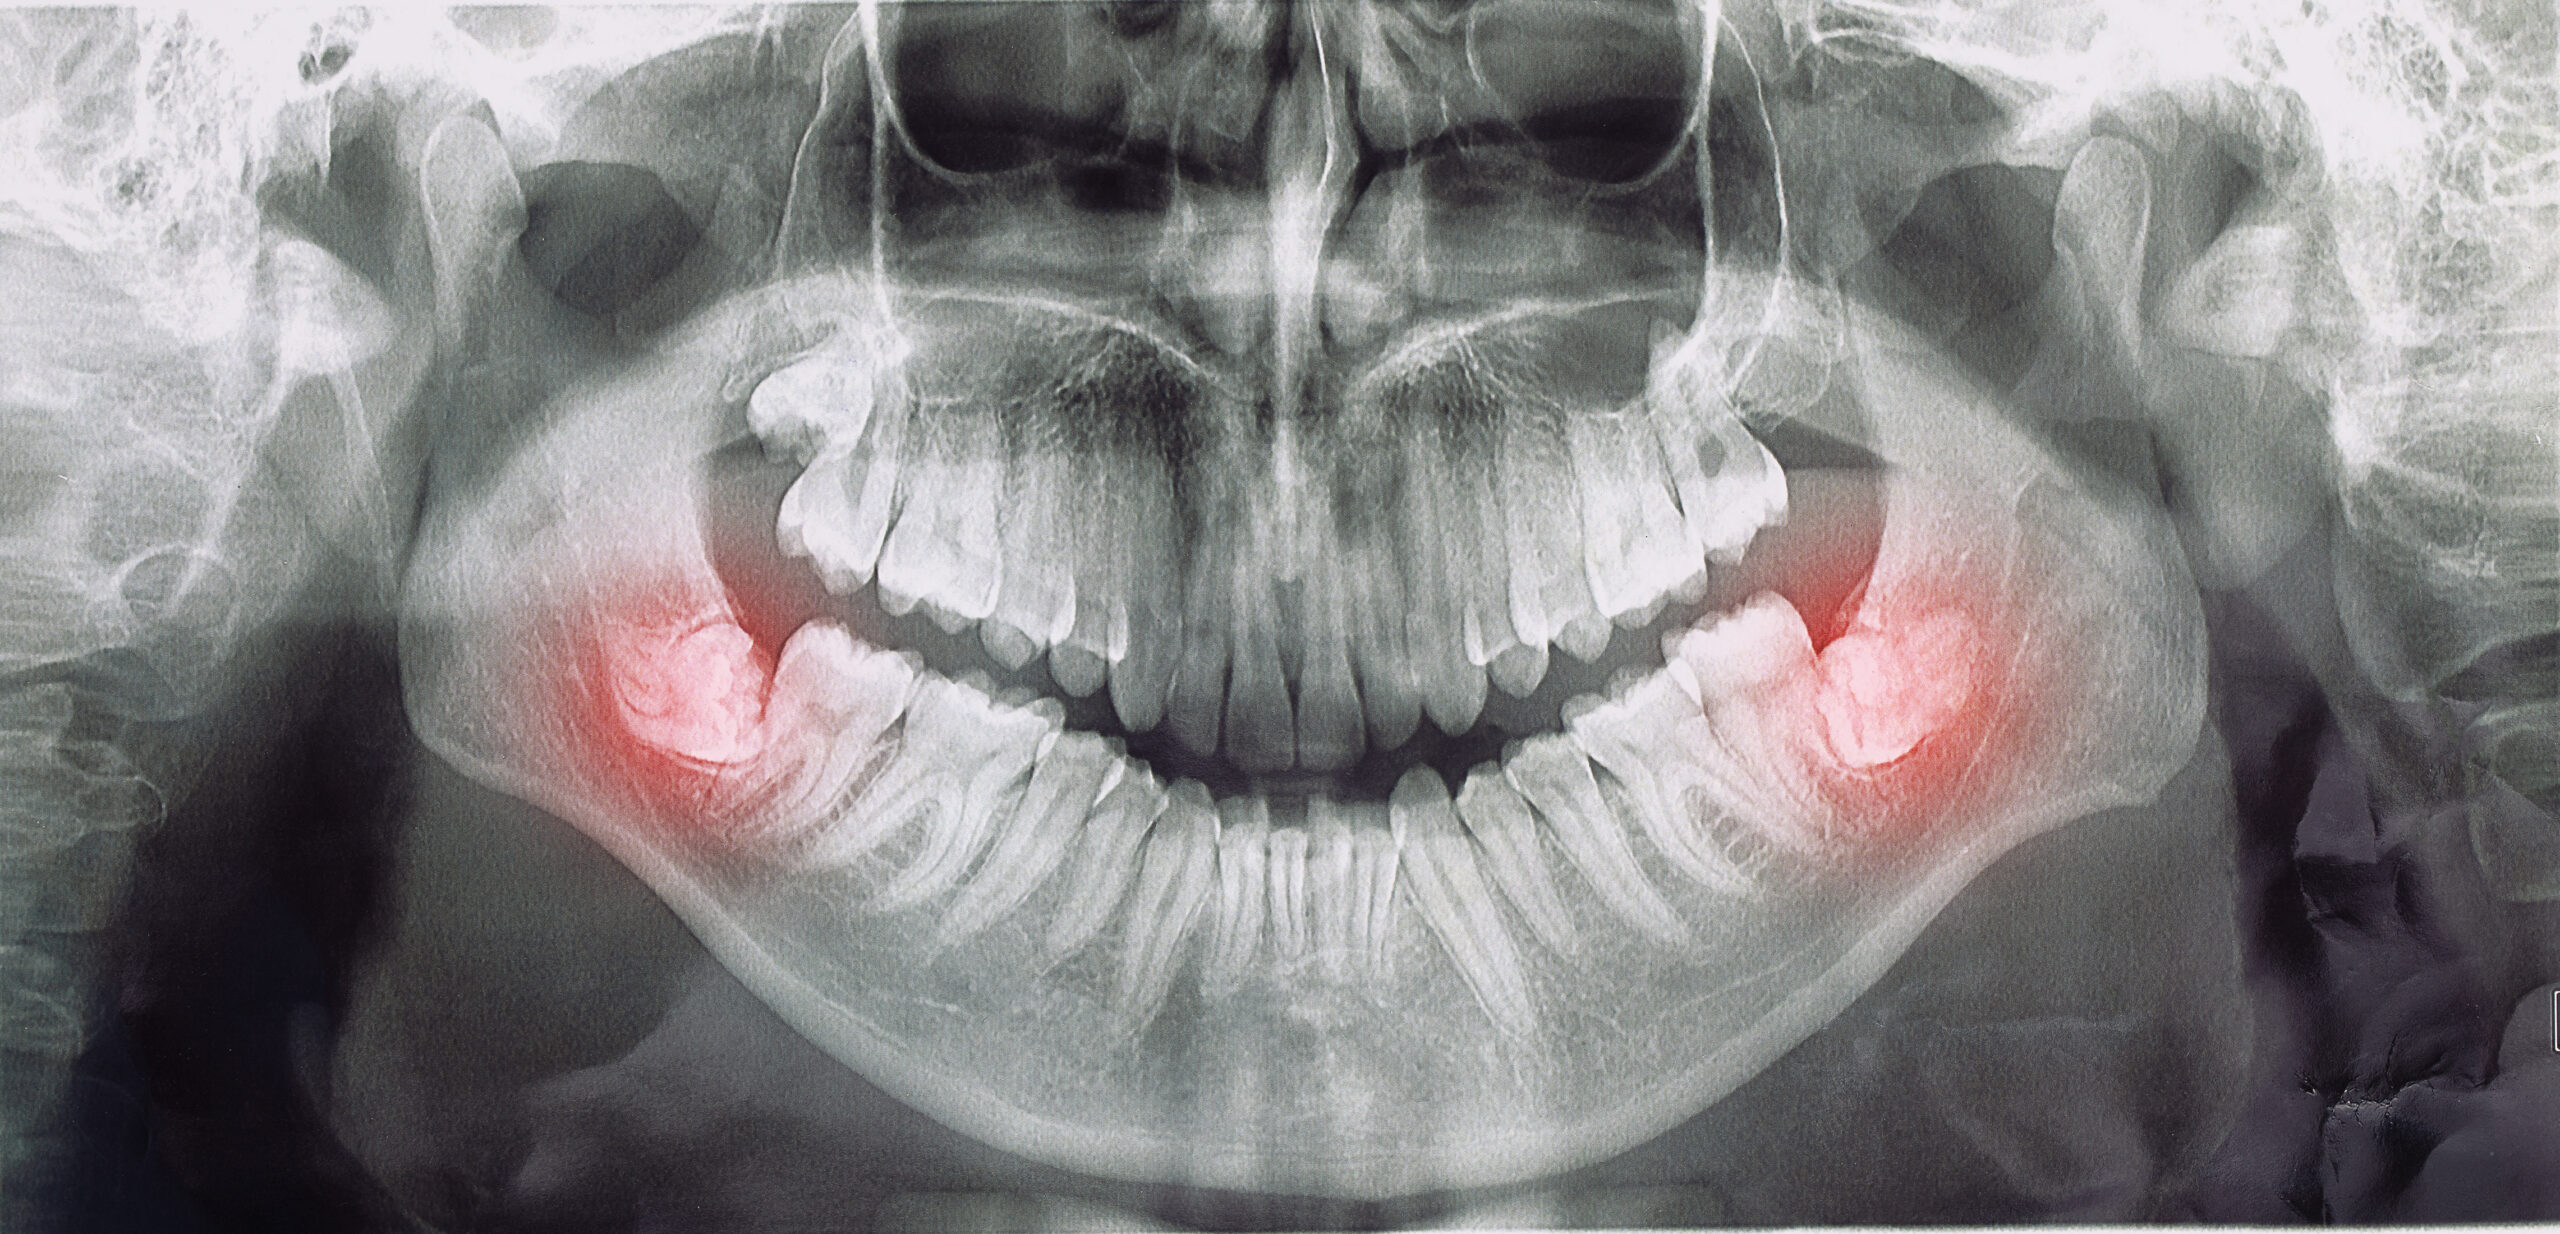

In which cases should impacted teeth be removed?

- Wisdom teeth, in particular, are frequently impacted due to a lack of space in our jaws. Semi-implanted wisdom teeth, or wisdom teeth with some visible inside the mouth and the rest under the gum, are susceptible to gingival infection. Food accumulation and compression are common under the gingiva from the part of the mouth that enters the mouth, and infections known as ‘pericoronitis’ are common in the gingiva and surrounding tissue in the region. Pericoronitis symptoms include redness around your wisdom tooth, swelling, a bad odor coming from the area, pain radiating to the ear, difficulty swallowing, and swelling in the lymph nodes.

- Presence of teeth that are at an angle to compress neighbouring teeth / have the potential to erupt / cause pressure-like pain

- They can cause cavities in neighboring teeth, as well as harm the roots of these teeth by pushing on them, produce pain or compress our other teeth, and induce crowding in the teeth.